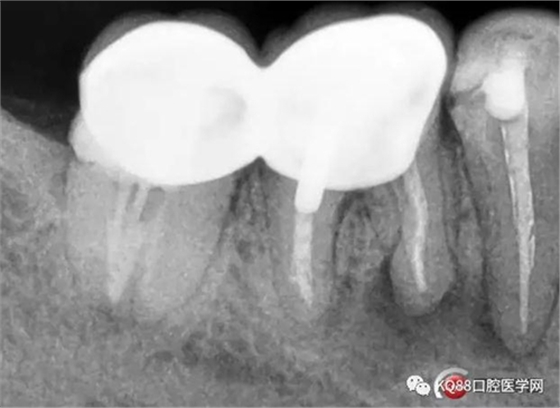

根充后X線片

46/47金瓷烤瓷聯(lián)冠修復(fù)后

(本病例系采用歐羅得卡大錐度根管銼機(jī)擴(kuò))